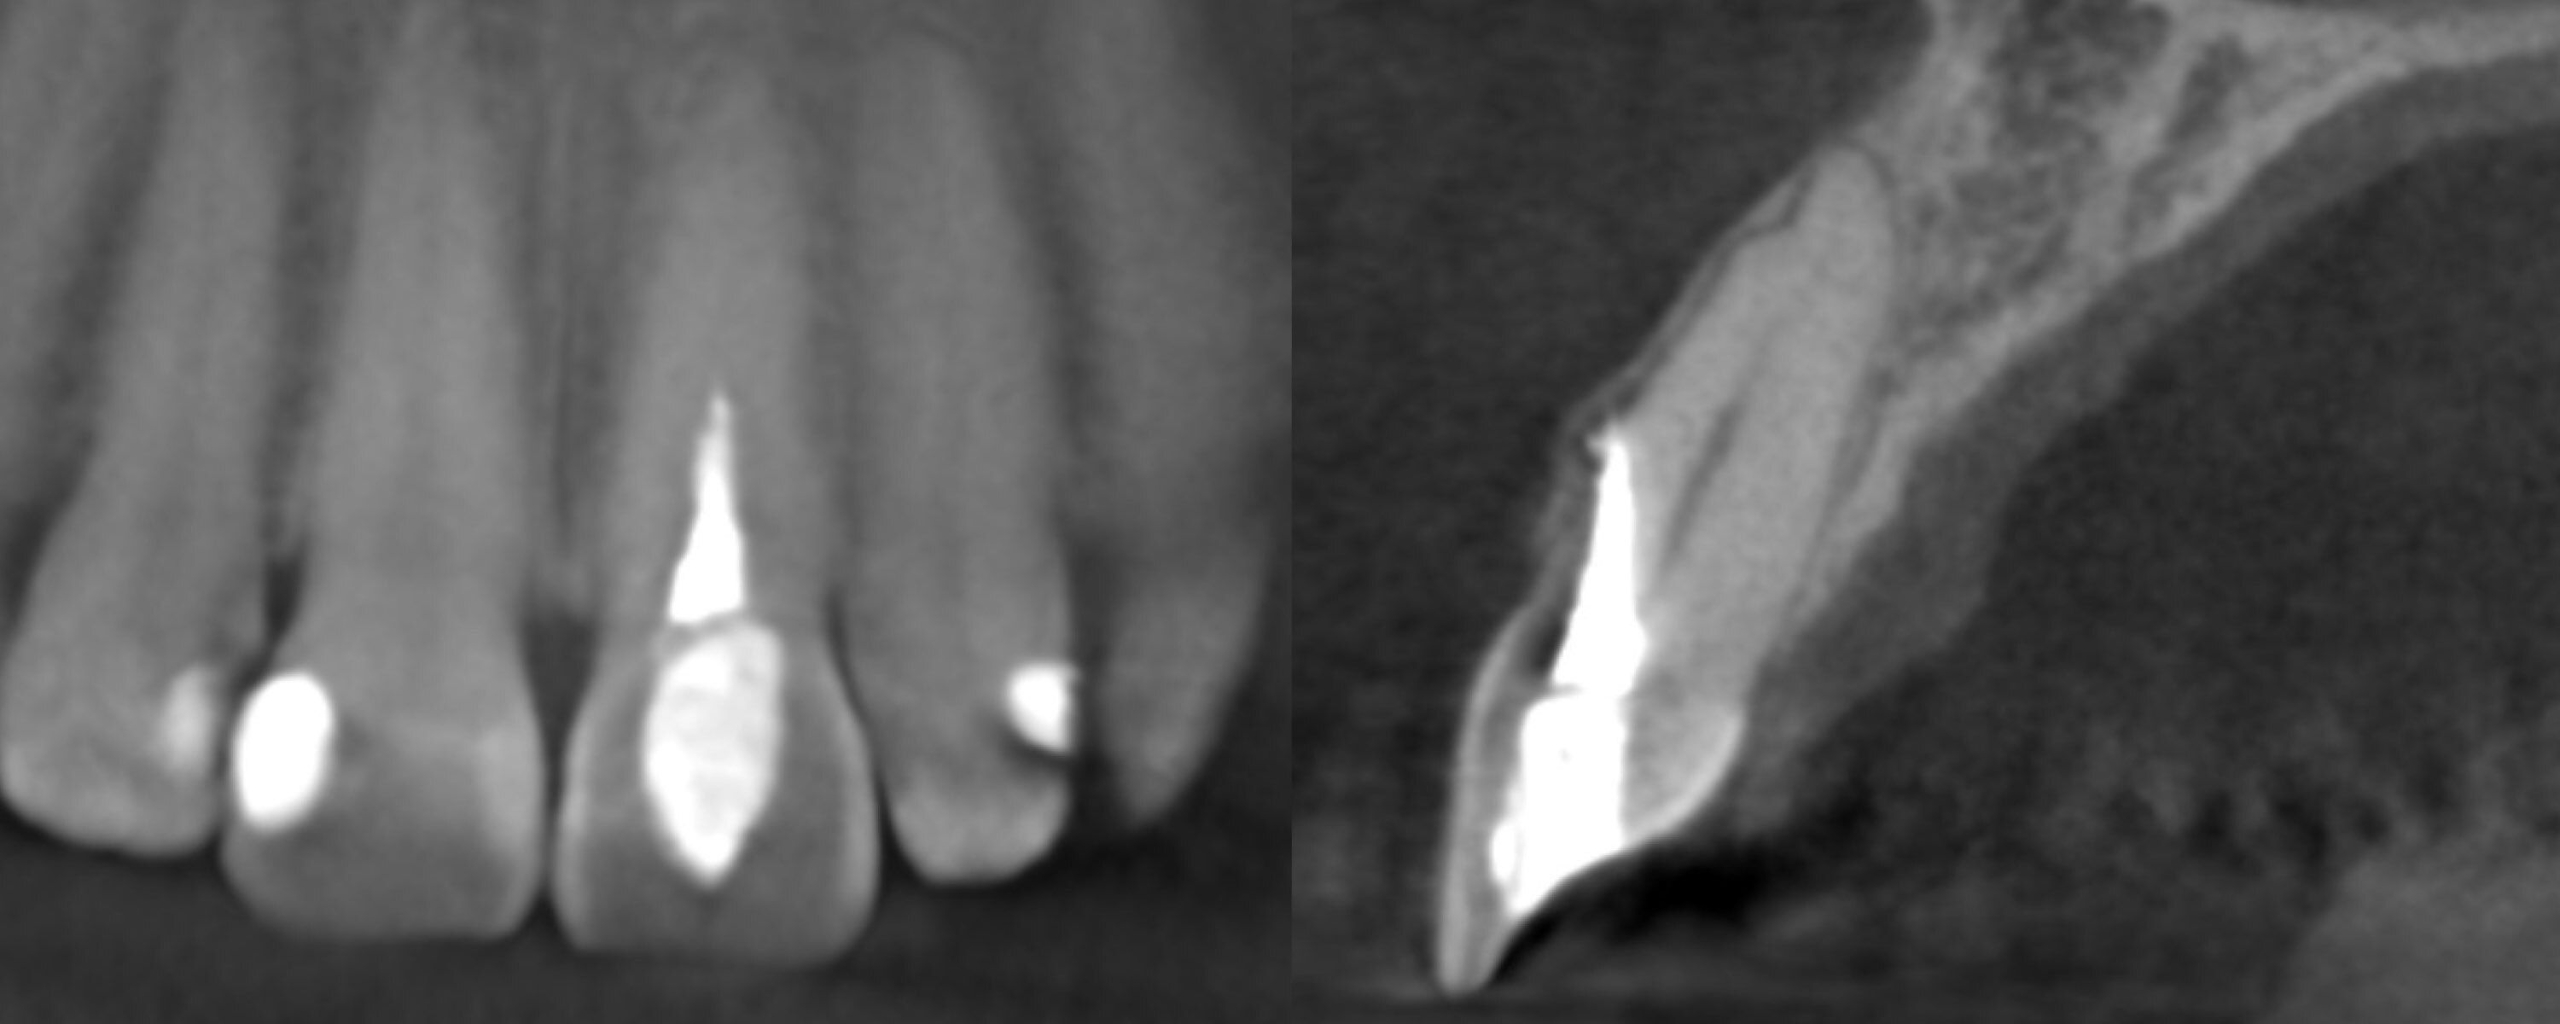

In this webinar, Dr. Ash Mark will tackle three of the most challenging endodontic complications: file fracture, perforation, and impassable ledged canals.